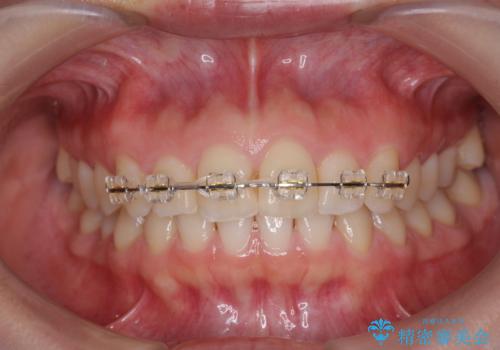

出っ歯に見える前歯の改善 部分ワイヤーとマウスピース矯正

- インビザライン +部分ワイヤー矯正

- 出っ歯に見える前歯の改善を希望され、来院されました。

マウスピースでは改善の難しい歯の動きを部分ワイヤー矯正で整えたのち、奥歯の噛み合わせや細かい歯の並びをマウスピース矯正インビザラインで整えていきます。

最終的な前歯の並びに大変満足いただくことができました。